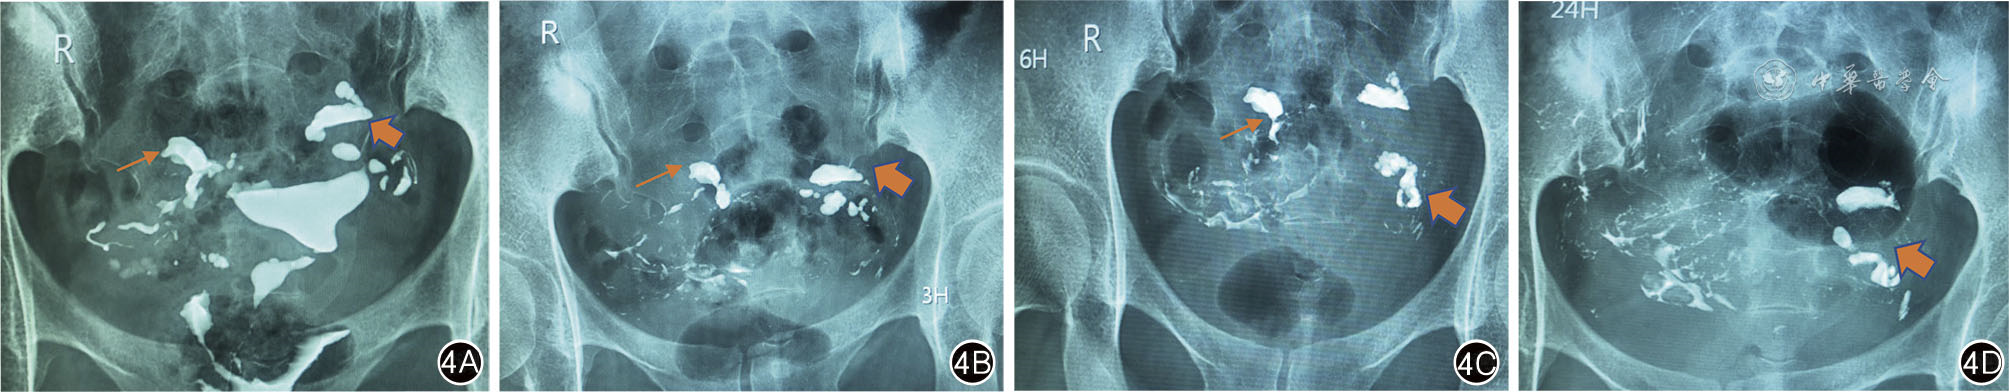

图4 左侧输卵管积水,右侧输卵管通畅 4A:充盈期,双侧输卵管远端管腔增粗(右侧输卵管细箭头,左侧输卵管粗箭头);4B~4C:延迟3、6 h片,双侧输卵管内见碘油滞留,远端管腔增粗,盆腔见碘油不均匀弥散;4D:延迟24 h片,左侧输卵管碘油滞留,远端管腔增粗(粗箭头),右侧输卵管内碘油溢出进入盆腔,盆腔见碘油广泛涂抹。24 h延迟片确认左侧输卵管积水,右侧输卵管通畅。